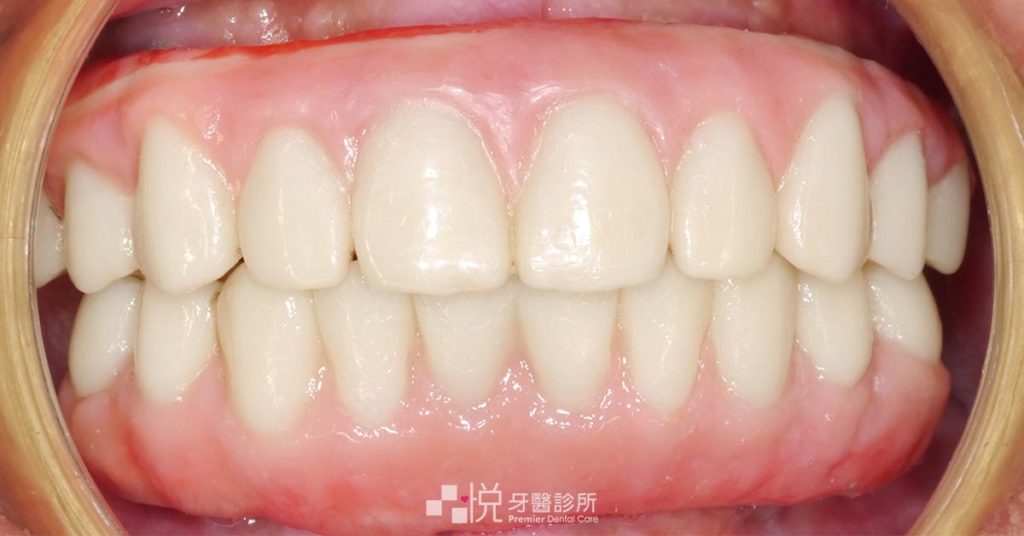

All-on-4 植牙手術復原後,陳媽媽原本看診時的表情僵硬也變成了開心的微笑,適應新假牙的生活,整個人都年輕了起來。